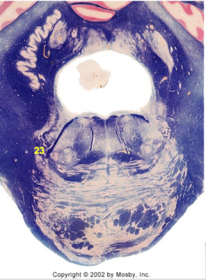

| Medullary pyramids | |

| Hypoglossal nucleus | |

| Hypoglossal nerve | |

| Dorsal motor nucleus of X | |

| Nucleus ambiguus | |

| Solitary tract | |

| Solitary nucleus | |

| ALS | |

| Medial lemniscus | |

| Medial longitudinal fasciculus | |

| Anterior spinocerebellar tract | |

| CN IX | |

| Inferior cerebellar peduncle | |

| Inferior olivary complex | |

| Dorsal cochlear nucleus | |

| Inferior vestibular nucleus | |

| Medial vestibular nucleus | |

| Spinal nucleus of V | |

| Spinal tract of V | |